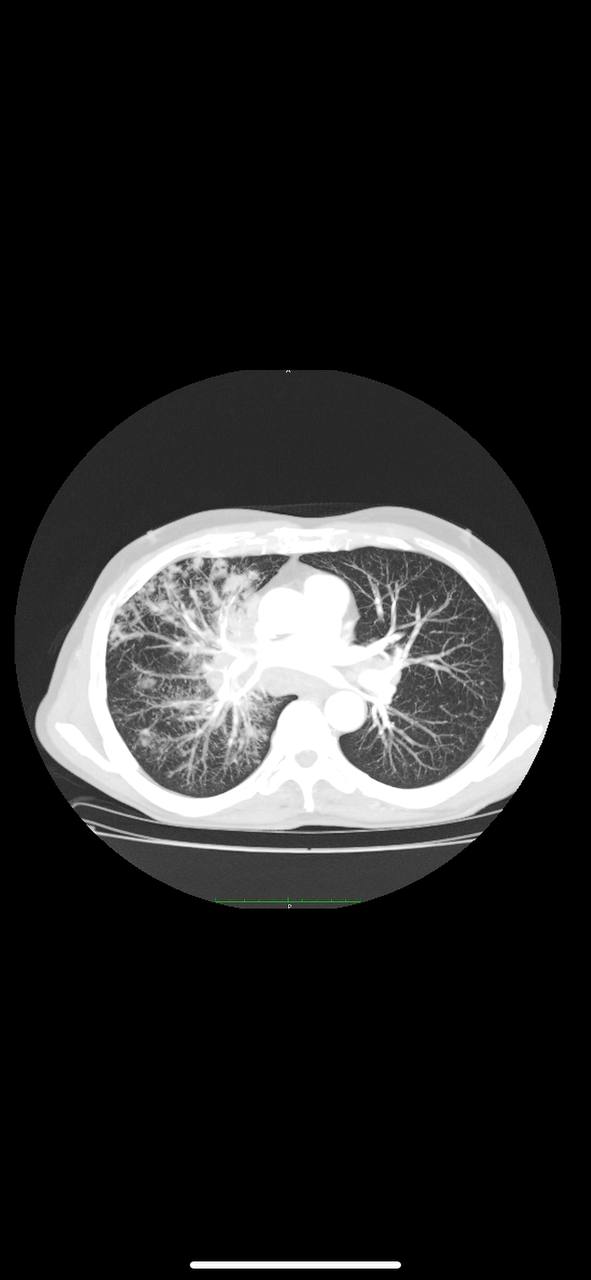

похоже на бронхоальвеолярный рак

Из учебника прям

петерн дерево в почках ,возможно инфекционка какаято